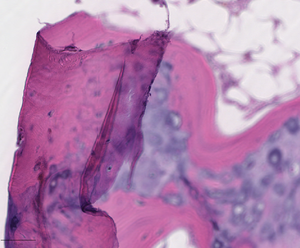

Trained pathologists traditionally view tissue slides under a microscope. These tissue slides may be stained to highlight cellular structures. When slides are digitized, they are able to be shared through tele-pathology and are numerically analyzed using computer algorithms. Algorithms can be used to automate the manual counting of structures, or for classifying the condition of tissue such as is used in grading tumors. They can additionally be used for feature detection of mitotic figures, epithelial cells, or tissue specific structures such as lung cancer nodules, glomeruli, or vessels, or estimation of molecular biomarkers such as mutated genes, tumor mutational burden, or transcriptional changes.[15][16][17] This has the potential to reduce human error and improve accuracy of diagnoses. Digital slides can be easily shared, increasing the potential for data usage in education as well as in consultations between expert pathologists. Multiplexed imaging (staining multiple markers on the same slide) allows pathologists to understand finer distribution of cell-types and their relative locations.[18] An understanding of the spatial distribution of cell-types or markers and pathways they express, can allow for prescription of targeted drugs or build combinational therapies in a personalized manner.

Digital slides are created from glass slides using specialized scanning machines. All high quality scans must be free of dust, scratches, and other obstructions. There are two common methods for digital slide scanning, tile-based scanning and line-based scanning.[5] Both technologies use an integrated camera and a motorized stage to move the slide around while parts of the tissue are imaged. Tile scanners capture square field-of-view images covering the entire tissue area on the slide, while line-scanners capture images of the tissue in long, uninterrupted stripes rather than tiles. In both cases, software associated with the scanner stitch the tiles or lines together into a single, seamless image.